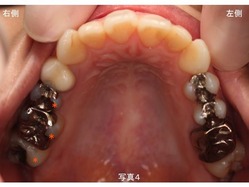

上下顎 左右側 ともに 多くの歯で金属製の詰め物や被せ物が装着してあります。

奥歯のみが噛み合っており、上下顎の前歯が噛み合っていないオープンバイトという状態です。

上顎右側の奥から4番目の歯は、白い状態に見えますが、これは仮歯のままです。